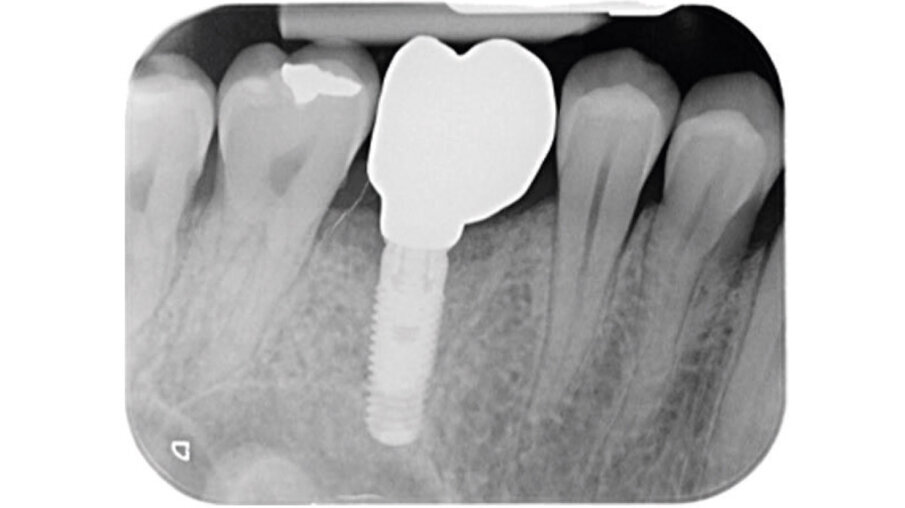

Un paziente maschio (ASA I), senza patologie croniche sistemiche e non fumatore, è stato sottoposto all’estrazione dell’elemento 16 a seguito del fallimento di terapie endodontiche e dell’impossibilità di eseguire un restauro coronale (Figg. 1a, 1b). Nella selezione del paziente sono stati criteri di esclusione: pregressa radioterapia nel distretto testa/collo, assunzione di farmaci che possano indurre ONJ, disordini ematici coagulativi, bruxismo, scarsa igiene orale domiciliare, occlusione instabile, carie non trattate, malattia parodontale non controllata, denti adiacenti a quelli da estrarre con mobilità di grado I o superiore, aspettative di risultato irreali, impossibilità o non propensi a tornare ai controlli di routine e di follow-up. La situazione dei tessuti è stata valutata pre-operatoriamente tramite radiografia periapicala (Fig. 1c) (VistaScan Mini Plus, Dürr Dental). Tramite la CBCT pre-operatoria è stato possibile fare una programmazione implantare. Sulla base dell’anatomia coronale è stata definita la posizione implantare (OnDemand3D, Cybermed), da questa analisi sono stati decisi anche il diametro e la lunghezza dell’impianto.

Fig. 1c_Foto iniziale, radiografia con cura canalare non ritrattabile, strumento rotto e probabile frattura verticale con sintomatologia da parte del paziente.